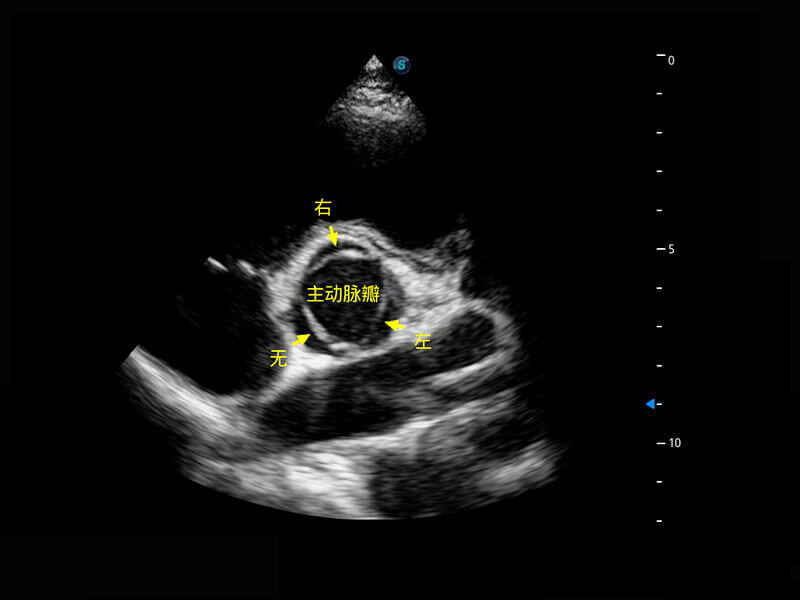

• 右室双出口

• 胎心容积成像